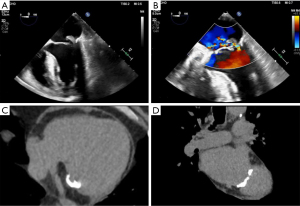

Mitral annular calcification (MAC) is associated with increased perioperative risks and can require conversion to valve replacement. A 67-year-old male with New York Heart Association (NYHA) class 2 dyspnea was found to have severe mitral regurgitation (MR) secondary to P2 leaflet prolapse. He had a history of hypertension, scleroderma, left below knee amputation, and gastrointestinal bleeding. Echocardiography & computed tomography (CT) imaging revealed a flail posterior leaflet with severe anteriorly directed jet of MR and severe posterior MAC (Figure 1). His ejection fraction was 60–65% with trace aortic and tricuspid insufficiency and no significant coronary artery disease. A minimally invasive mitral valve repair using a novel ultrasonic emulsification and aspiration technique using the Sonopet device (Stryker, Michigan) was planned.